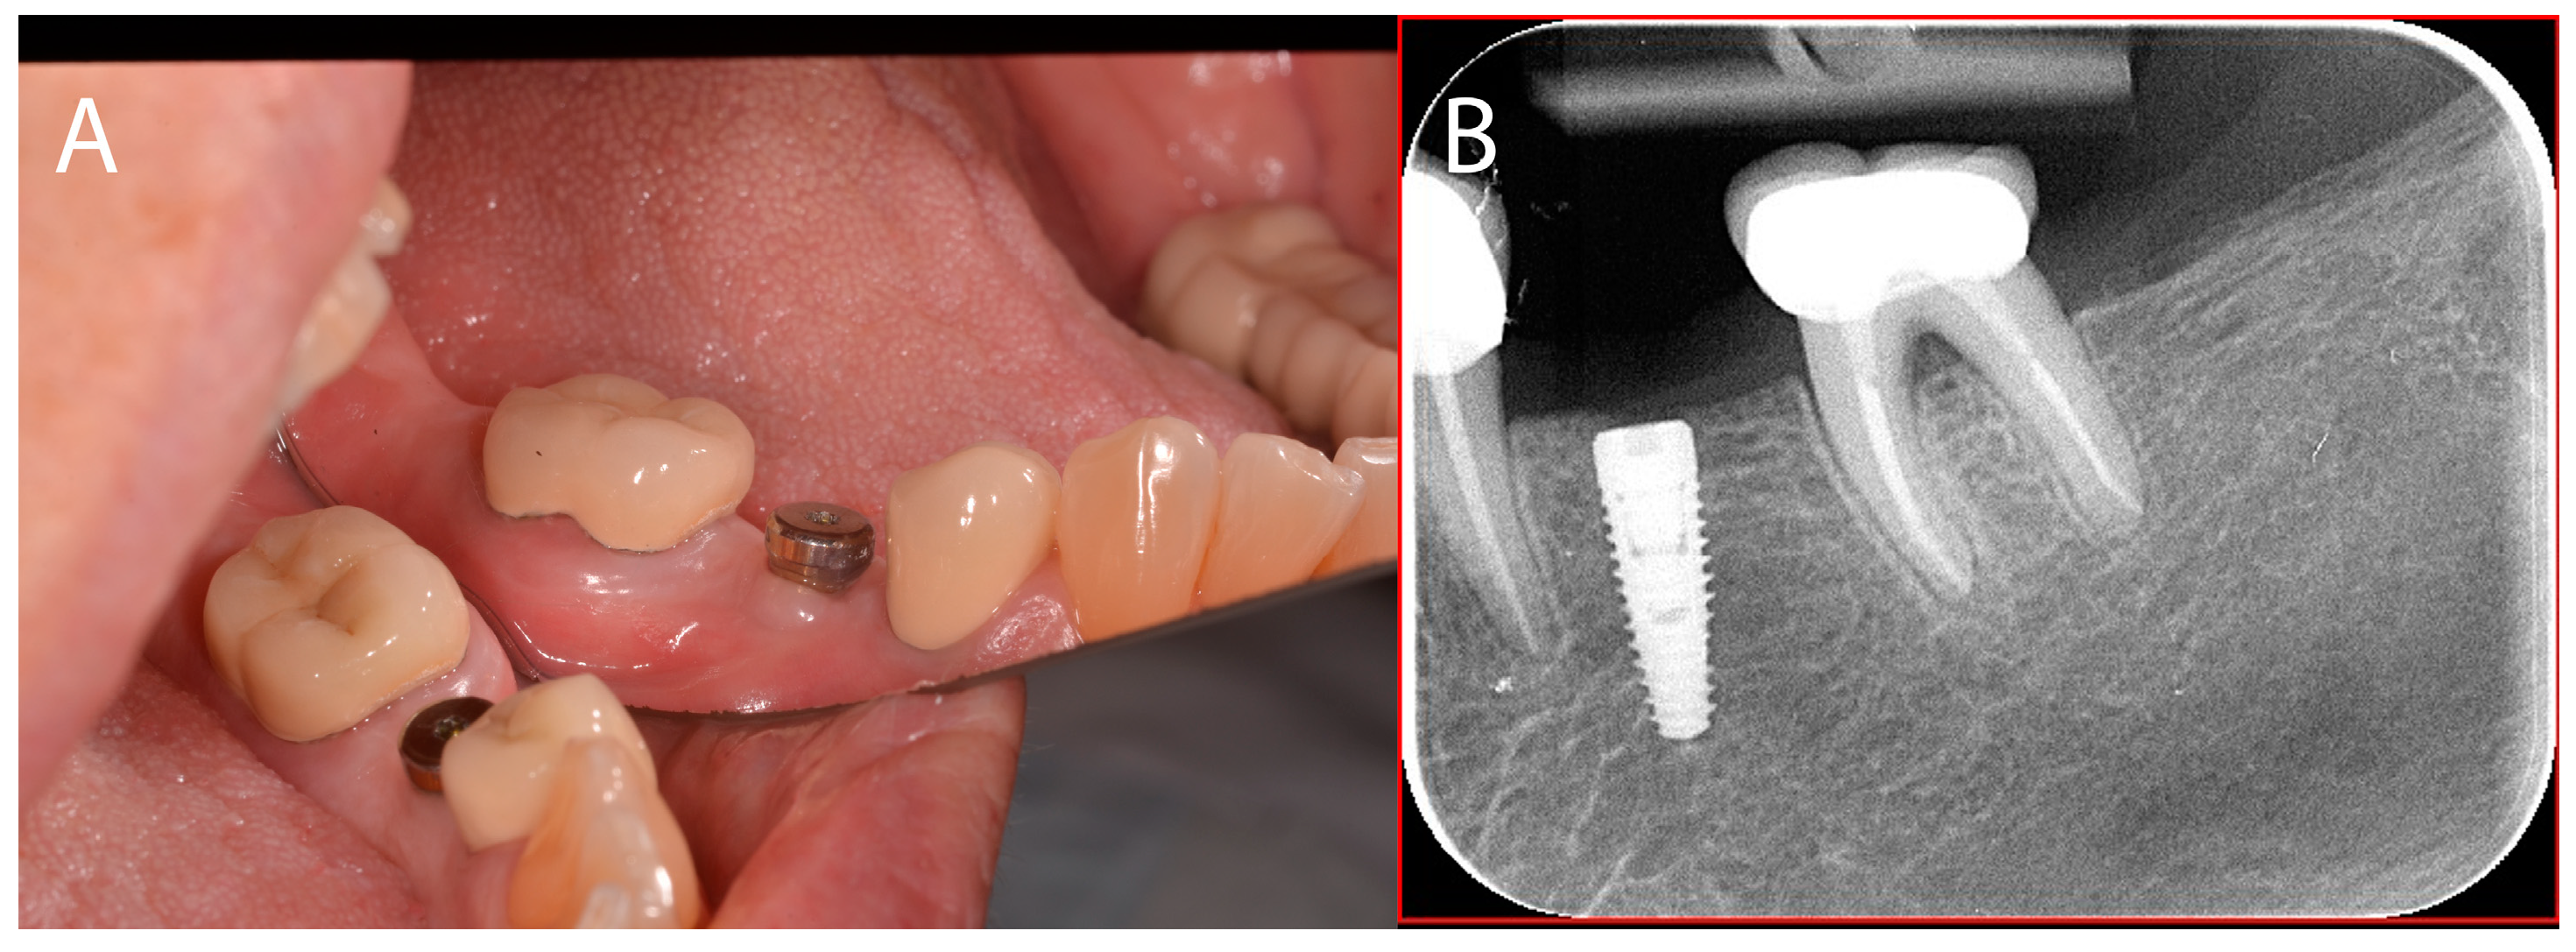

2.3. Case Presentation #2

2.3.1. Anamnesis, Physical Examination

2.3.2. Treatment